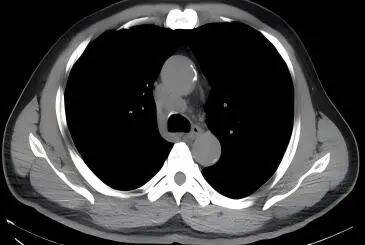

2022-09-20  颈部+胸部CT增强示:右锁骨上下窝见多发肿大淋巴结影,较大者约22×21mm;右肺上叶前段实性结节,大小约为17×8mm ;纵隔内见肿大淋巴结影,大小约11×23mm。

影像学检查图像(基线)